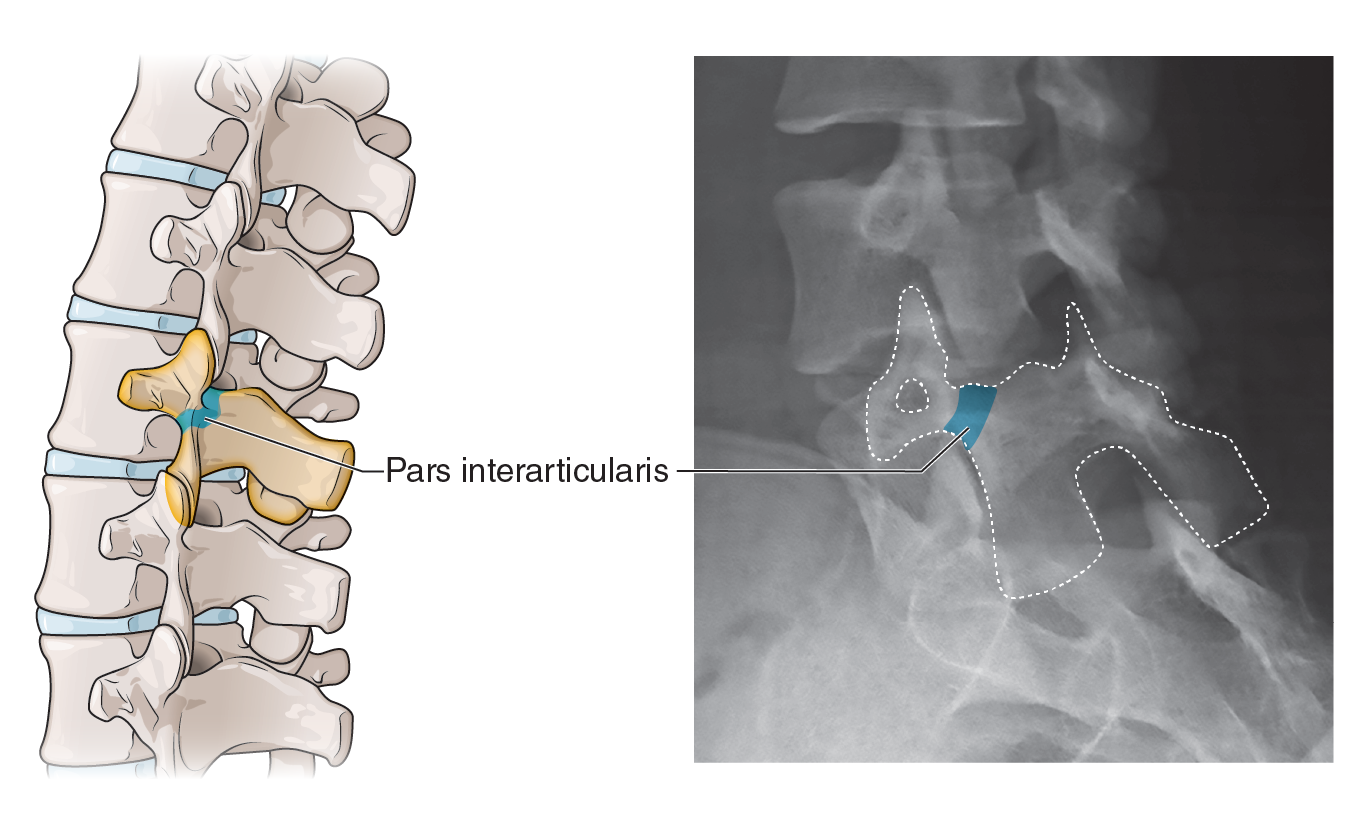

Textbook illustration

I have nearly twenty years of experience in text book publishing, having illustrated books from grade school to graduate level, and in subject areas from human anatomy to biology and geology. I never say no to projects involving dinosaurs.

Patient education

Illustrations can help patients understand surgical procedures they or a loved one are planning to have, or explain how a medication works in the body.